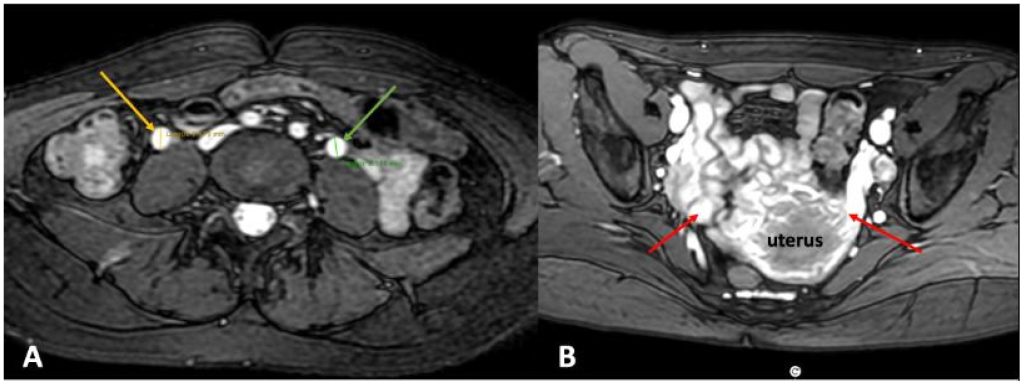

2.3.1. Компьютерная томография (КТ) и магнитно-резонансная венография (МРВ) играют ключевую роль в выявлении расширенных яичниковых вен и тазовых сплетений. Эти методы диагностики помогают обнаружить сопутствующие тромботические окклюзии, коллатеральные отводящие сосуды и другие патологии, вызывающие симптомы..

Рисунок 5. (А) Расширенные яичниковые вены: левая 9,1 мм (зеленая стрелка), а правая — 9,9 мм (желтая стрелка). (B) Варикозные вены в периматочном венозном сплетении (красные стрелки).